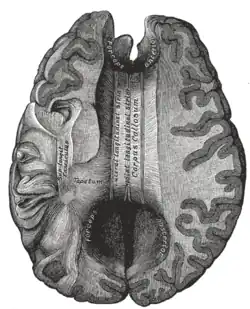

![]() Corpus callosum from above, front part at the top of the image. | |

The corpus callosum (Latin for "tough body"), also callosal commissure, is a wide, thick nerve tract, consisting of a flat bundle of commissural fibers, beneath the cerebral cortex in the brain. The corpus callosum is only found in placental mammals.[1] It spans part of the longitudinal fissure, connecting the left and right cerebral hemispheres, enabling communication between them. It is the largest white matter structure in the human brain, about 10 in (250 mm) in length and consisting of 200–300 million axonal projections.[2][3]

The corpus callosum forms the floor of the longitudinal fissure that separates the two cerebral hemispheres. Part of the corpus callosum forms the roof of the lateral ventricles.[5]

On either side of the corpus callosum, the fibers radiate in the white matter and pass to the various parts of the cerebral cortex; those curving forward from the genu into the frontal lobes constitute the forceps minor (also forceps anterior) and those curving backward from the splenium into the occipital lobes, the forceps major (also forceps posterior).[4] Between these two parts is the main body of the fibers, which constitute the tapetum and extend laterally on either side into the temporal lobe, and cover in the central part of the lateral ventricle. The tapetum and anterior commissure share the function of connecting left and right temporal lobes.